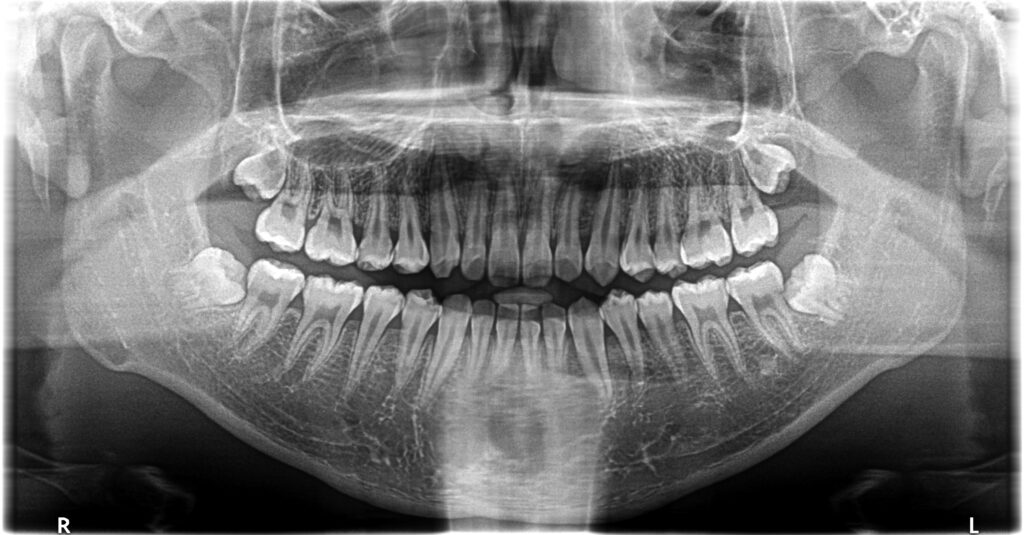

治療6年後

高校2年生で下の左右の埋伏の親知らずを抜歯しました。下の埋伏親知らずは、将来の歯並びの予後に悪い影響を与えたり、年齢が上がるにつれて抜きにくくなるので、できれば早期の抜歯が望ましいと考えています。一方、上の親知らずのは抜歯は簡単なことが多く、手前の7番や開咬などの不正咬合に悪い影響をあたえなければ、下程急ぐ必要はないかもしれません。当医院では一応下の親知らずの抜歯をもって、ある程度の矯正は終了と捉えています。しかし、管理されるのが嫌、抜きたくない方、他(高次機関等)で抜歯したいという方は13歳位で1期治療は終了という方針です。